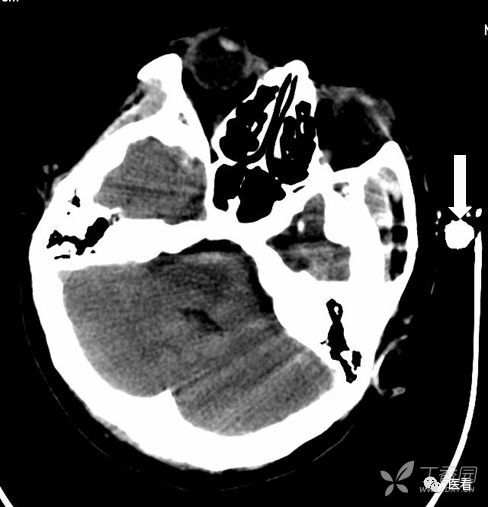

亨氏暗区

颅底(致密)骨产生的横行或放射状伪影,与设备性能也有关系

下图为16拍MSCT,伪影较轻。

此图为双排螺旋 CT图像, 伪影较16层及以上MSCT显著的多。